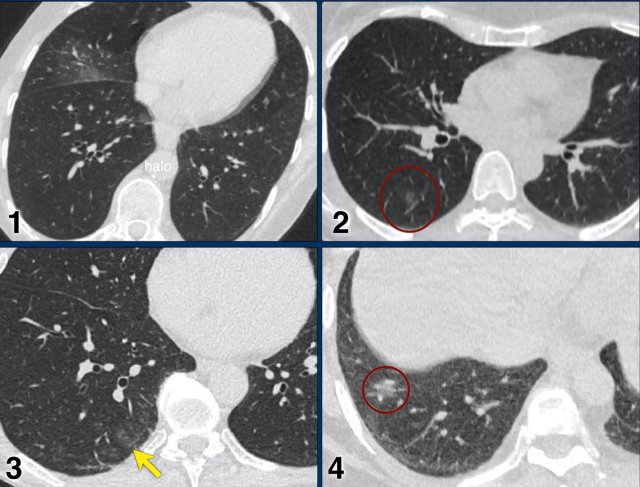

Examples of CO-RADS 3. Click to enlarge. Examples of CO-RADS 3. Click to enlarge.

CORADS 3

COVID-19 unsure or indeterminate.

CT abnormalities indicating infection, but unsure whether COVID-19 is involved, like widespread bronchopneumonia, lobar pneumonia, septic emboli with ground glass opacities.

Case 1.

One day complaints. CT: Unifocal GGO. PCR negative.

Case 2.

CT: Unifocal GGO (circle).

Case 3.

CT: Unifocal GGO (arrow).

Case 4.